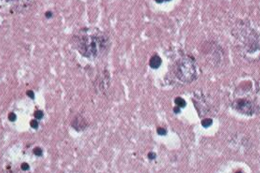

Гистологические изменения характеризуются развитием диссеминиро-ванного негнойного полиэнцефаломиелита лимфоцитарного типа. Пато-гномоничное значение при бешенстве имеет образование в цитоплазме ганглиозных клеток специфических телец-включений Бабеша-Негри округлой или овальной формы, содержащих базофильные зернистые образования вирусных нуклеокапсидов различной структуры.

В) Обнаружение специфических телец-включений. Приготовленные мазки-отпечатки окрашивают по Серерсу, Муромцеву или другими методами. Препараты после окрашивания просматривают в световом микроскопе с иммерсионной системой. Положительным результатом считают наличие специфических телец Бабеша-Негри. Это четко очерченные овальные или продолговатые гранулярные образования розово-красного цвета в протоплазме (при окраске по Селерсу); при окраске по Муромцеву - тельца Бабеша-Негри светло-фиолетовые с темно-синими включениями, чаще они располагаются вне нервных клеток. Тельца Бабеша-Негри выявляют лишь в 65 - 85 % случаев бешенства. Поэтому отсутствие их не является отрицательным ответом и материал исследуют в других тестах (РИФ, РДП, биопроба) .

Посмертно исследуют срезы аммоновых рогов головного мозга и обнаруживают в них специфические включения - тельца Бабеша-Негри. Тельца Бабеша-Негри также присутствуют в цитоплазме нейронов, гиппокампе, клетках Пуркинье коры мозжечка, стволе мозга, гипоталамусе и спинномозговых ганглиях. Данные тельца присутствуют в головном мозге только при бешенстве, наличие их при других заболеваниях, в том числе и при заболеваниях центральной нервной системы, не зафиксировано.

Состоят тельца Бабеша-Негри из тонковолокнистого матрикса и вирусного рибонуклеопротеида, размер телец - около 10 нанометров.

Тельца Бабеша-Негри